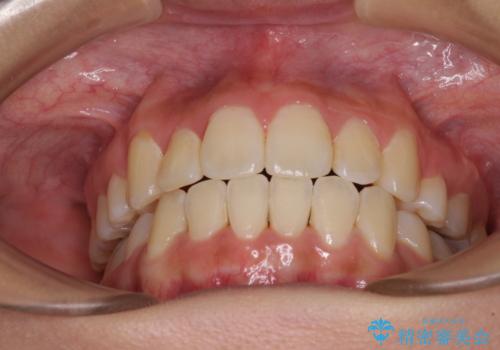

前歯の正中のズレを改善 目立たないワイヤー装置での抜歯矯正

移動量が多かったため、治療期間は通常より半年~1年ほど長くかかりましたが、上下の正中をほぼ同じ位置にまで移動させることができました。